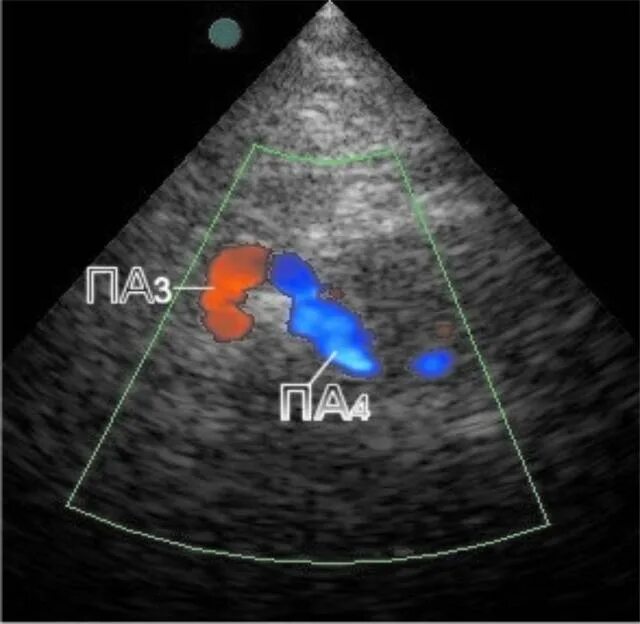

Асимметрия сегментов v2 позвоночных артерий